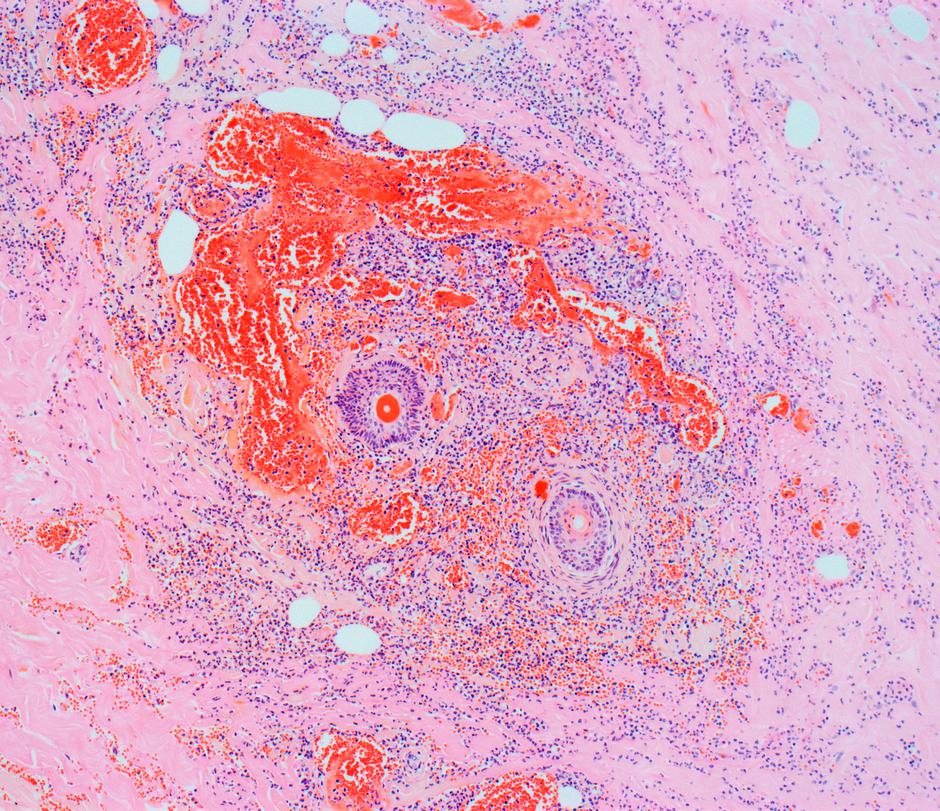

V bolnišnici so zdravniki kaj hitro odkrili, da je Heather utpela redko bakterijsko okužbo, imenovano nekrotizirajoči fasciitis, kjer so bakterije pričele razžirati njeno tkivo.

Nekrotizirajoča okužba mehkih tkiv je sicer redka, vendar zelo huda vrsta bakterijske okužbe. Lahko uniči mišice, kožo in tkivo. Beseda "nekrotiziranje" se nanaša na nekaj, kar povzroči, da telesno tkivo umre.

Nekrotizirajoči fasciitis

Bolezen v glavnem povzročajo bakterije streptokoki, podobne tistim, ki povzročajo gnojno angino; so zelo agresivne in sproščajo veliko bakterijskih strupov (toksinov). Bakteriji pravijo tudi mesojeda, čeprav ne napada mišic, ampak mišične ovojnice.

Človek zboli, ko se bakterije naselijo na mišičnih ovojnicah; tam se razraščajo in sproščajo velike količine toksinov, ki povzročijo propad mišične ovojnice in prek krvi zastrupljajo celotno telo. Zbolijo lahko vsi ljudje, ne glede na starost, vendar le tisti, ki imajo oslabljen imunski sistem zaradi akutne ali kronične bolezni.